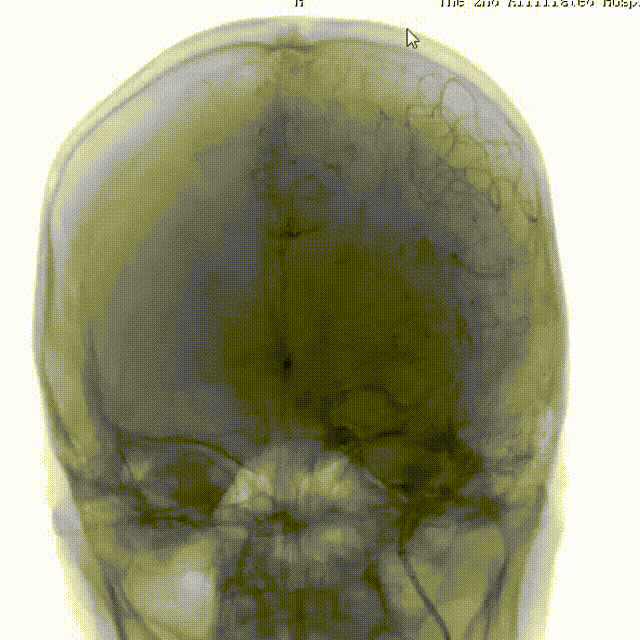

DWI:双侧侧脑室旁及左侧颞叶见多发斑点状、结节状、斑片状DWI高信号,双侧侧脑室旁及颞叶病变ADC呈低信号影,左侧基底节区病变ADC呈稍高信号影。

术后CT结果: